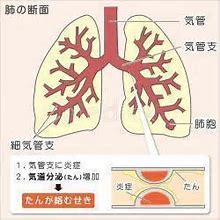

気管・気管支! 気管支炎ってどうなってる?いつも違うたんが出るときは要注意!

COPDの気管支・肺胞の解説。気管支壁が炎症によってむくんだり、たんなどの分泌物が気管支内に大量に出ることにより、空気の通り道がふさがら、呼吸がしにくくなる。気管支の先にあり、酸素を取り込む場所であるぶどうの房状の肺胞が炎症によって壊され、酸素を取り込みにくくなり、呼吸が苦しくなる。